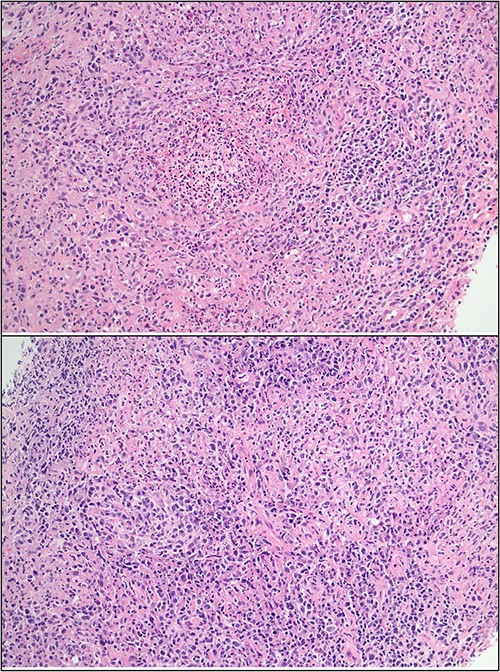

Ultrasound of the right axillary mass indicated a single enlarged lymph node measuring 26 × 25 × 40 mm (Fig. 1). Following discussion with haematology and infectious disease specialists, a nodal core biopsy was performed. This identified an atypical lymphoid infiltrate primarily characterized by CD138+/IRF4+ plasma cell clusters, interspersed by CD3+/CD5+ T cells and scattered necrotic foci (Fig. 2). As this was a core biopsy, nodal architecture was not appreciable. There was mild positivity for plasma cells on EBV-encoded small RNA in situ hybridization (EBER-ISH), consistent with the patient’s positive EBV PCR status. Bacterial and fungal specimen culture was negative, including for Mycobacterium tuberculosis, and flow cytometry did not detect any monotypic B cells or aberrant T cells.

Core biopsy histology showing lymphoid infiltrate with foci of suppuration and dense plasma infiltrate.

Additional PCR testing for B. henselae and Toxoplasma gondii was conducted on the core biopsy specimen, and B. henselae DNA was detected. To investigate the possibility of comorbid PTLD, excisional node biopsy was performed. Histology demonstrated histiocytic granulomas with a surrounding lymphoid infiltrate; crucially, there was no effacement of nodal architecture on the full specimen (Fig. 4). At this stage, serum B. henselae IgG was repeated and returned a positive result (>1: 1024; cut-off 1: 256), indicating seroconversion within the 15-day period from his negative B. henselae IgG at admission.

Excisional biopsy histology (A) foci of necrotising granulomatous inflammation; (B) presence of EBER-ish-positive cells.